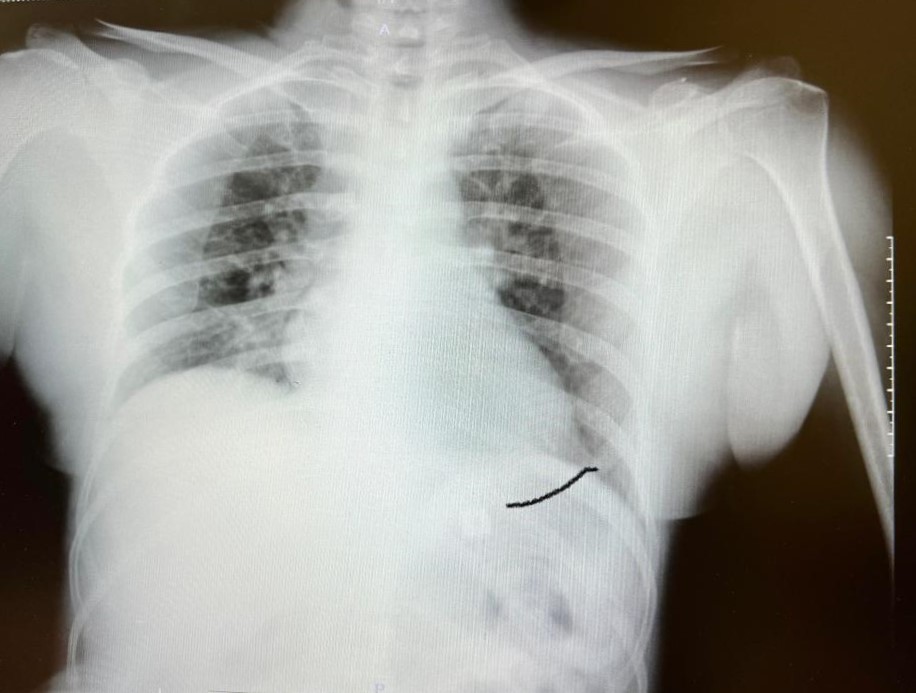

Yoğun bakıma alınan hastayayaptığımız detaylı tetkikler ve klinik değerlendirme sonucu mediyastenit (ciddi göğüs enfeksiyonu) saptandı. Bu ciddi bir sorun olup, hayati riski yüksektir. En hızlı şekilde tıbbi tedaviye başladık,gastroenteroloji bölümümüzde endoskopi yapıldı.

Yemek borusunda oluşan delik ve delikten mideye inen metalik cerrahi aparat görüldü. Göğüs kafesi içinde ciddi bir iltihap ve hava birikimi vardı. Hasta yakınları durum ile ilgili bilgilendirildi, riskler kendileri ile paylaşılarak hastamıza tıbbi müdahale edebilmemiz gerekli onayları alındı.”

“Yaklaşık 6 saat süren bir ameliyat oldu. Hastamıza ilk endoskopik yol ile göğüs orta bölümdeki (mediasten ki bu bölgeye insan hayatının makine dairesi deriz) cerahat boşaltılıp tahliye edildi. Daha sonra boyun bölgesindeki biriken iltihaptemizlendi. Yemek borundaki 2 cm’lik perforasyon (delik) tespiti ve tamiriyapıldı” diyen Prof. Dr. Elbeyli, şu bilgileri paylaştı:

Hastanın şikayetleri üzerine endoskopi (cerrahi müdahale olmaksızın sindirim sistemini incelemek amacıyla hastanın ağızdan girilmesi şeklindeyapılan işlem) yaptıklarını anlatan Doç. Dr. Yılmaz, şu bilgileri aktardı:

“Endoskopi sırasında hastanın midesinde metalik bir oluşuma benzer yabancı cisim ile yemek borusunda ülser görünümüizledik. Lezyon bölgesi belirlendikten sonra hastamızıntedavisi için Göğüs Cerrahisi Bölümümüze durumu ilettik. Prof. Dr. Levent Elbeyli Hocamız hastamızın sağlığına kavuşması için gerekli tedaviyi planlayarak, başarılı bir operasyonla sonuca ulaştı. Emeği geçen herkese teşekkür ediyorum. Hastamızı sağlıklı bir ömür diliyorum.”